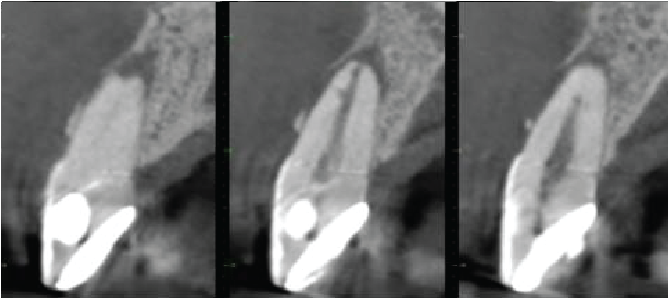

Cross sectional images of UR1

Mesio-distal

Labio-palatal

The UR1 is heavily restored. The root canal is patent, with a lateral canal directed mesiolabially 3mm from the root apex. A periapical granuloma is extending down the mesial and labial sides of the root, with a fenestration of the labial cortical plate. There is apical inflammatory root resorption.